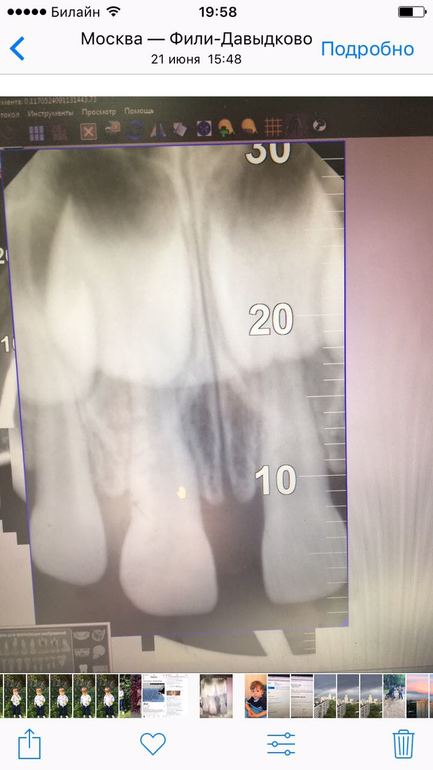

очень нужна еще одна консультация стоматолога, помогите, пожалуйста, ребенок несколько месяцев назад упал и ударился зубом, он потемнел, сходили сделали снимок, сказали, что связка повреждена и наблюдать, вот вчера еще раз сходили сделали снимок и сказали, что есть небольшая подвижность и что корень этого зуба уменьшается и нужно удалять((((((( ребенку 2г11 мес. Подскажите, пожалуйста, действительно нужно удалять?

прилагаю фото двух рентгенов

Не вижу показаний к удалению зуба.

Да, корень стал короче. Но это не повод лишаться зуба

Я бы рекомендовала удалить нерв из зуба и запломбировать канал. Возможно, когда-нибудь все же потребуется удалить. Что мало вероятно. В моей практике такие зубы менялись по возрасту самостоятельно.